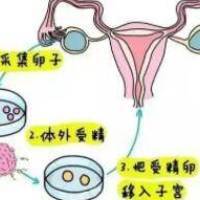

三代试管全流程细致解说(2025版)

1. 前期检查与个体化方案订定

夫妻两方需实现染色体解析、激素六项、精液常规等检查,明的确是否存在遗传性疾病携带或生殖系统问题。高龄女性需额定评介卵巢储存功能(如AMH检查),为促排方案设计提供依照。

3. 取卵取精与胚胎培育

在超声疏导下穿刺取卵,同时获得精子。选用显微授精(ICSI)技术提高受精比率,受精卵培育5-6天造成囊胚,保障结构稳定。

5. 移植与妊娠管理

筛选后的合格胚胎移移植同步进程处置的子宫腔,术后通过黄体酮药物支持着床。移植后14天验血HCG确认妊娠,成功后转入高风险产科跟踪随访。